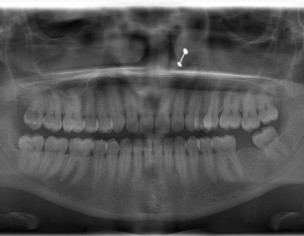

Please have a look at my xray and let me know how many of my teeth have cavity and what should be the next procedure

what are your symptoms?where do you feel pain? according to xray you have one large cavity in the right upper back tooth. Rest teeth condition is not cleared in the xray. sometimes small caries are not detected in this large OPG xray.

Hope you are doing well. Multiple teeth are carious according to this OPG.. Your right upper and lower third molars are grossly carious.. Might need extraction.. Rest I think you have pit and fissure lesions in lower right and left 1st molars (need clinical assessment for that). Also there is evident bone loss in some region especially lower anterior region and I can see some calculus deposits so scaling may also be required. Also there is missing tooth in lower left side for which you need replacement. So get yourself checked and managed accordingly

Yes dr, I visited dental surgeon and he said 3 of my wisdom tooth have cavity and it all needs to be extracted and he will extract the 4rth tooth as well otherwise it will create problems later. Also i knwo about the scalling part my front lower teeth has plaque i will deal that later.

But the reason to post here is i feel apart from those teeth i think other of my teeth has problem too i dont know what and which

I told you rest of the problems too.. There is also signs of mal-alignment so if you want.. You can get braces treatment too.. No other major cavities

So apart from all 4 wisdom teeth, no other teeth has cavity?

I cannot see all third molars carious.. I think upper left one is okay (from the xray) but intra oral exam is a good judge for that or a peri apical radiograph.. I think you might have pit and fissure caries in your lower first molars that's all